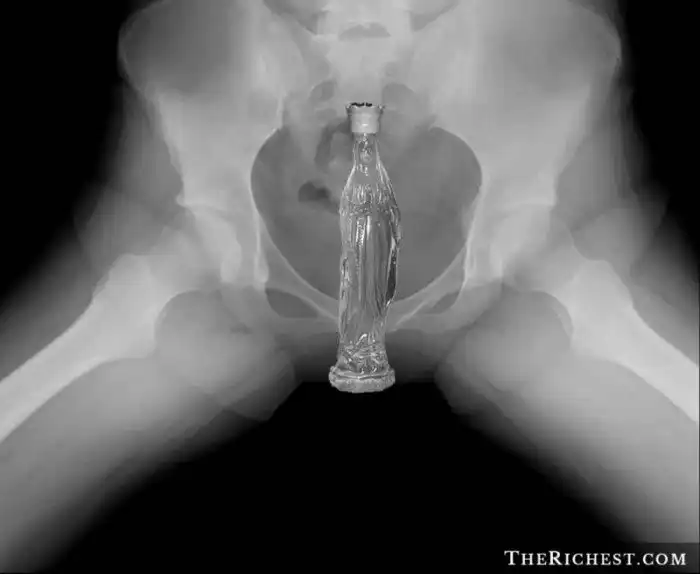

Бутылка колы

В заднем проходе 60-летнего мужчины была обнаружена бутылка колы. По словам пострадавшего, накануне его дом обокрали, а воры надругались над ним с помощью злосчастной бутылки.